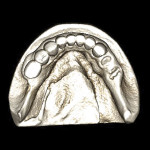

While CBCT provides insight into the 3-D assessment of the mandible or maxilla for implant placement, it does not do the best job of replicating the surface detail of teeth or surrounding anatomical structures. Surface data acquisition can be accomplished by using one of three methods: (1.) placing a stone cast into an optical scanner to capture the surface detail and occlusal morphology; (2.) placing a stone cast into the same CBCT scan machine with the same settings as the patient’s scan; or (3.) using intraoral scanners to take a virtual impression of the patient’s dentition. The majority of clinical applications use a stone cast fabricated from an intraoral impression with standard trays and impression materials (Figure 1). The diagnostic process has been further enhanced by the development of software applications that allow data from different sources to be combined. Merging the digital information from either method (optical or DICOM) with the original CBCT data greatly enhances the diagnostic phase and improves restoratively driven treatment planning (Figure 2).